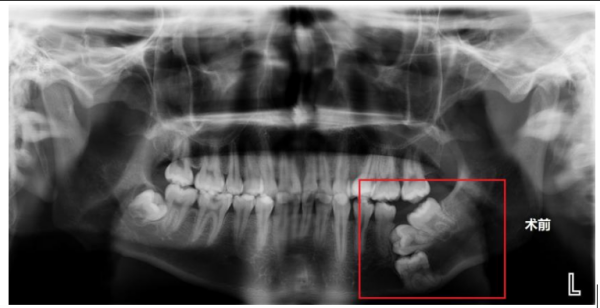

术前X片显示,右下颌骨内没长出来的三颗磨牙呈“叠罗汉”状埋伏

据了解,家住益阳市的王其(化名)自6岁起左下磨牙一直未萌出,家长起初以为仅是发育较晚,未予重视。直至14岁时,王其的磨牙仍未见生长,父母这才带着他去当地立博体育

检查,完善了口腔X片后才发现,王其多年无牙的罪魁祸首竟是其右下颌骨内没长出来的三颗磨牙呈“叠罗汉”状埋伏,由于埋伏牙位置较深,当地立博体育

建议在面部下方皮肤行切口拔除埋伏牙,或者继续观察,等待恒牙自行萌出。因考虑传统手术可能遗留面部瘢痕,王其及家人选择保守观察。